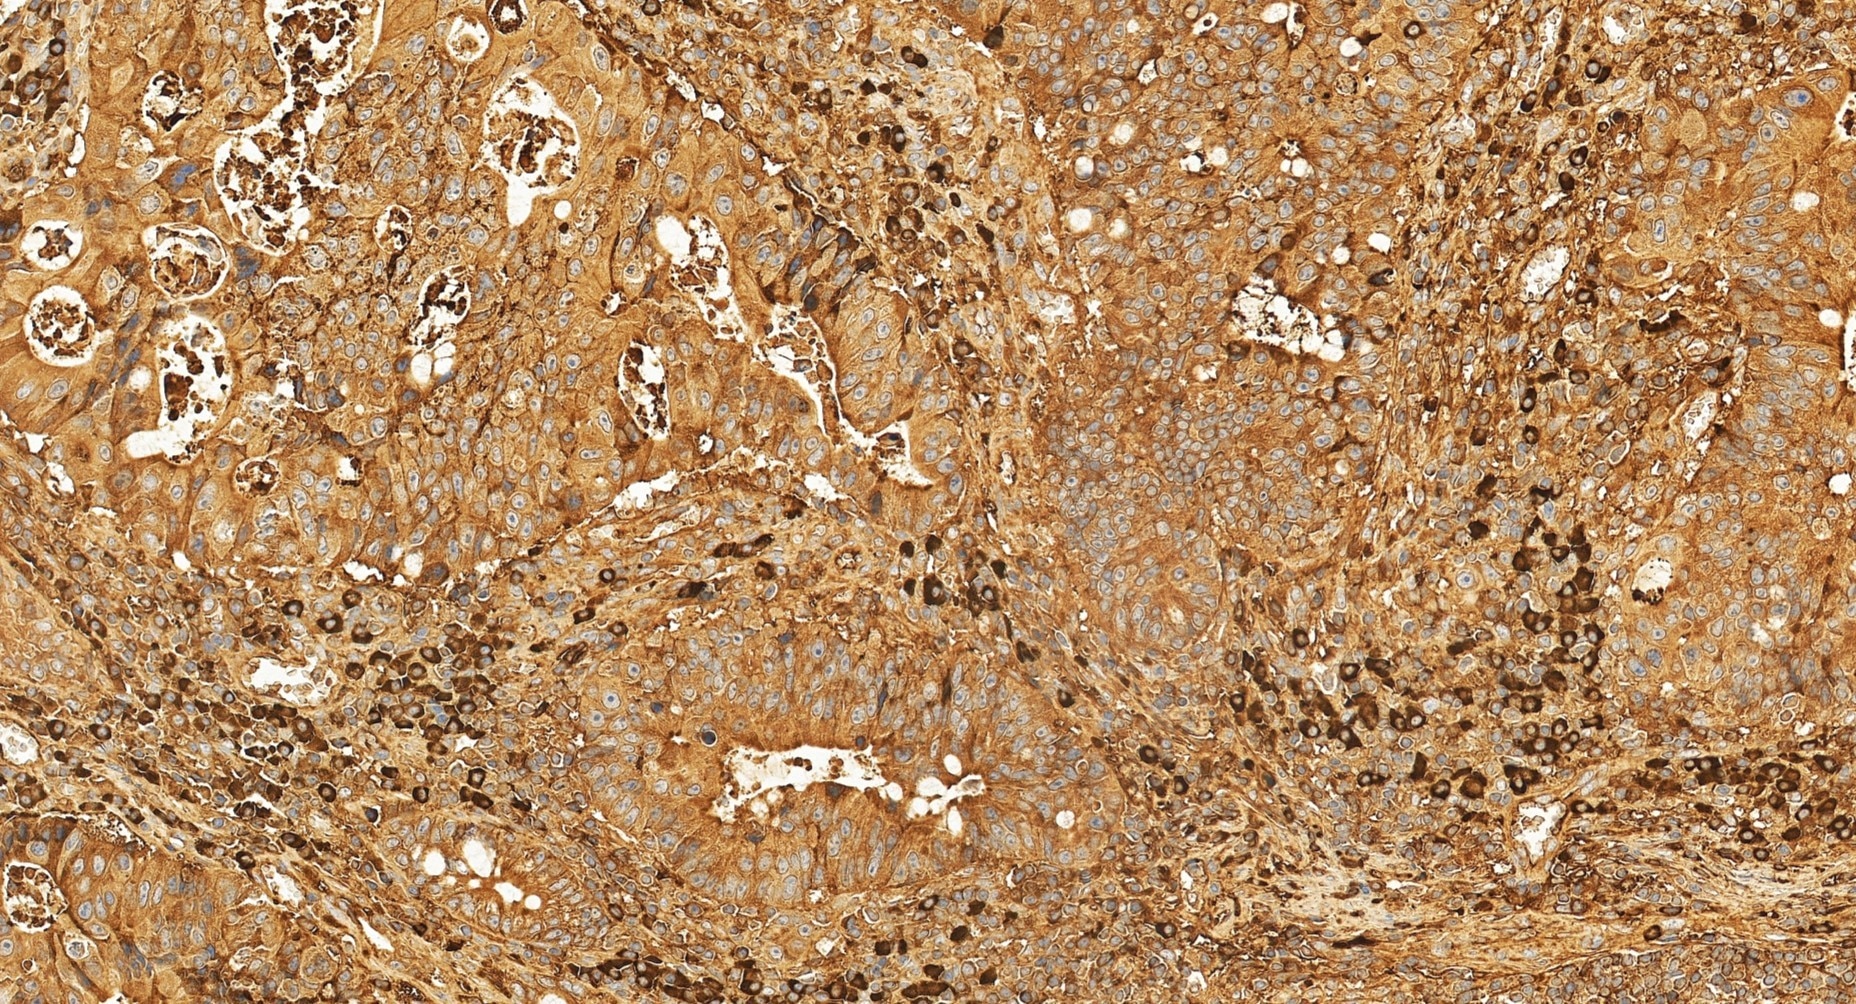

| Positive IHC detected in | human colon cancer tissue Note: suggested antigen retrieval with TE buffer pH 9.0; (*) Alternatively, antigen retrieval may be performed with citrate buffer pH 6.0 |

| Immunohistochemistry (IHC) | IHC : 1:50-1:500 |